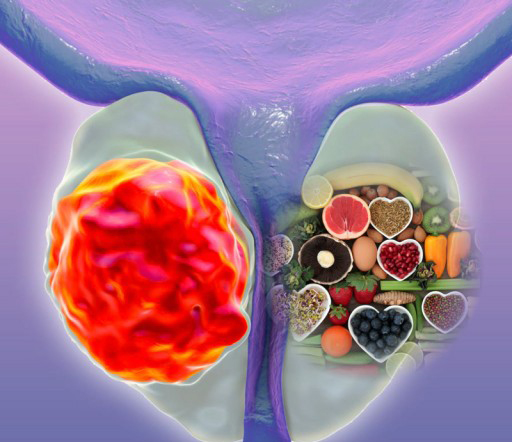

전립선에 좋은 음식 나이가 들면서 전립선 비대증이나 전립선암과 같은 질환에 노출될 위험이 커지므로, 평소 식단 관리를 통해 전립선 건강을 챙기는 것이 매우 중요합니다. 지금부터 전립선 건강을 지키는 10가지 효과적인 음식을 꼼꼼히 살펴보고, 건강을 위한 첫걸음을 함께 시작해 볼까요? 👨⚕️

전립선에 좋은 음식

전립선 건강을 위해서는 항산화 물질, 미네랄, 건강한 지방이 풍부한 식품을 섭취하는 것이 좋습니다. 다음은 전문가들이 추천하는 10가지 식품입니다.